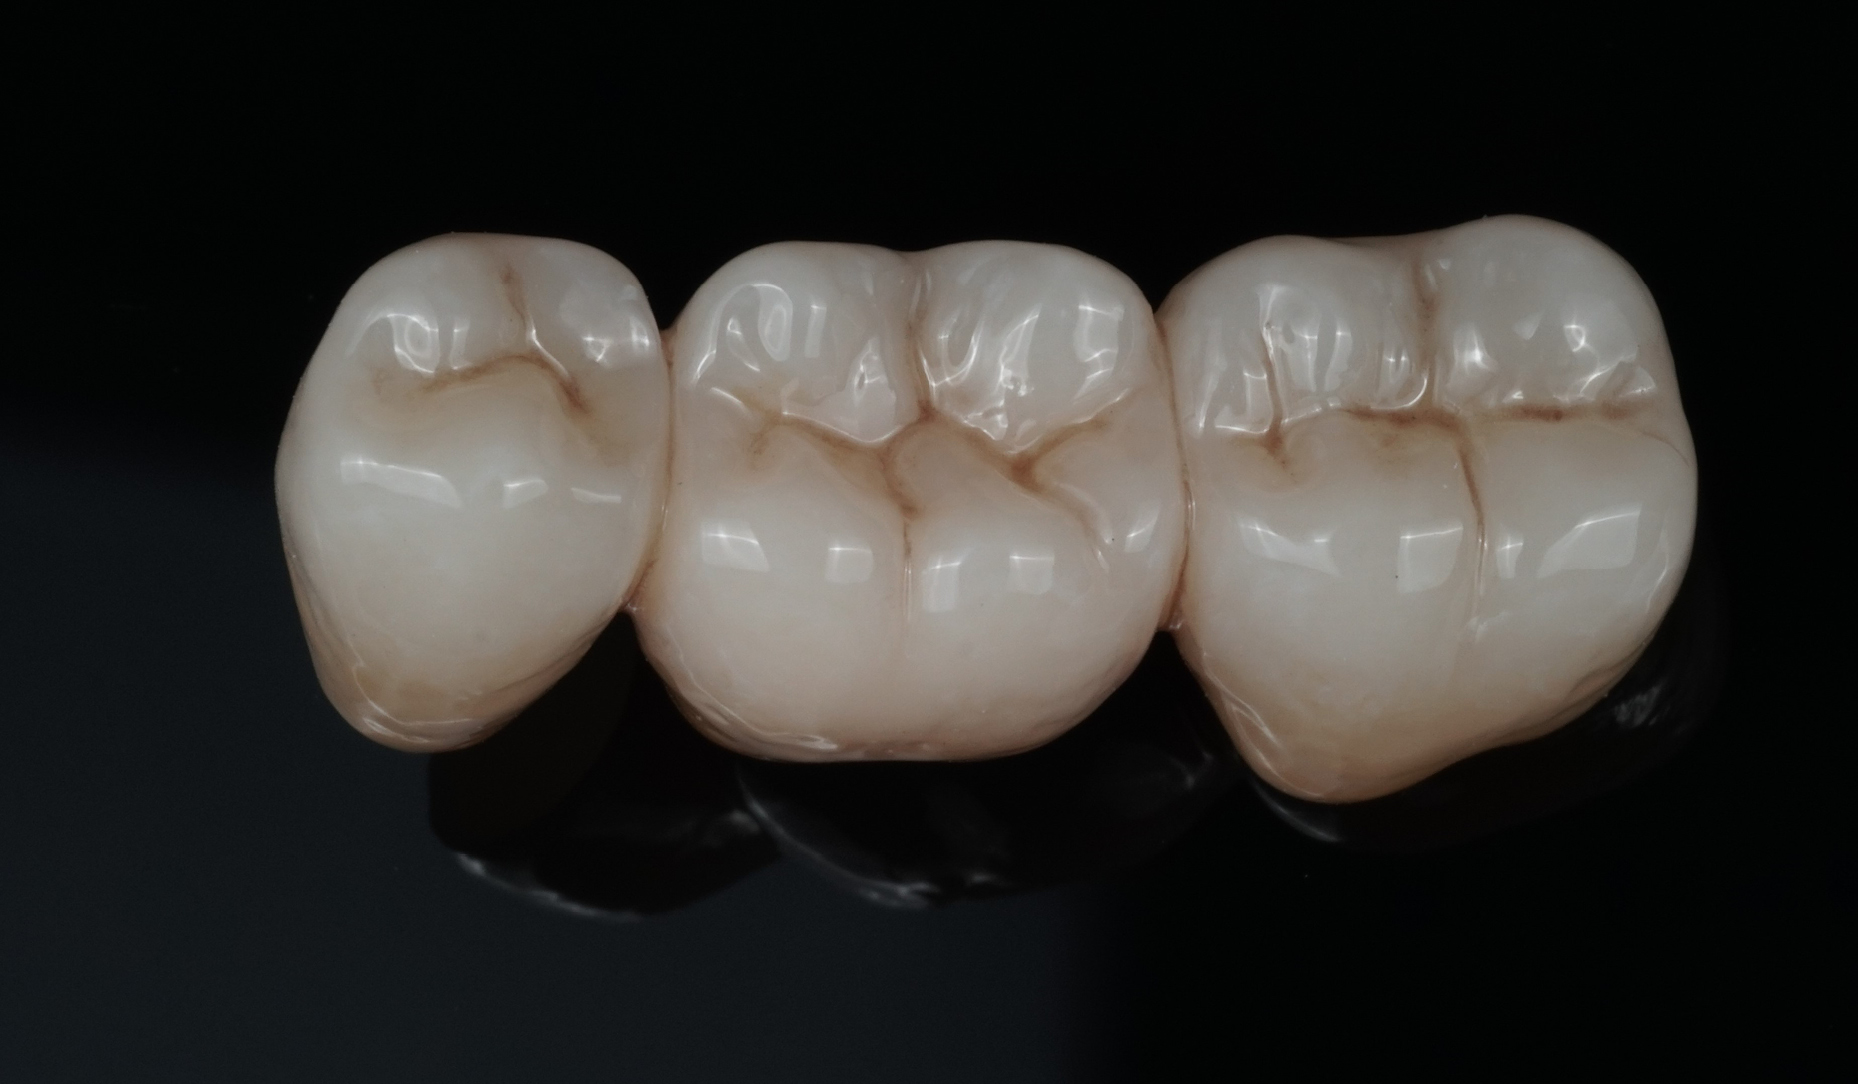

Ryc. 9. Wygląd mostu po indywidualizacji za pomocą płynnej ceramiki CERABIEN™ ZR FC Paste Stain...

Ryc. 10. ... oraz po dwóch wypaleniach glazury.